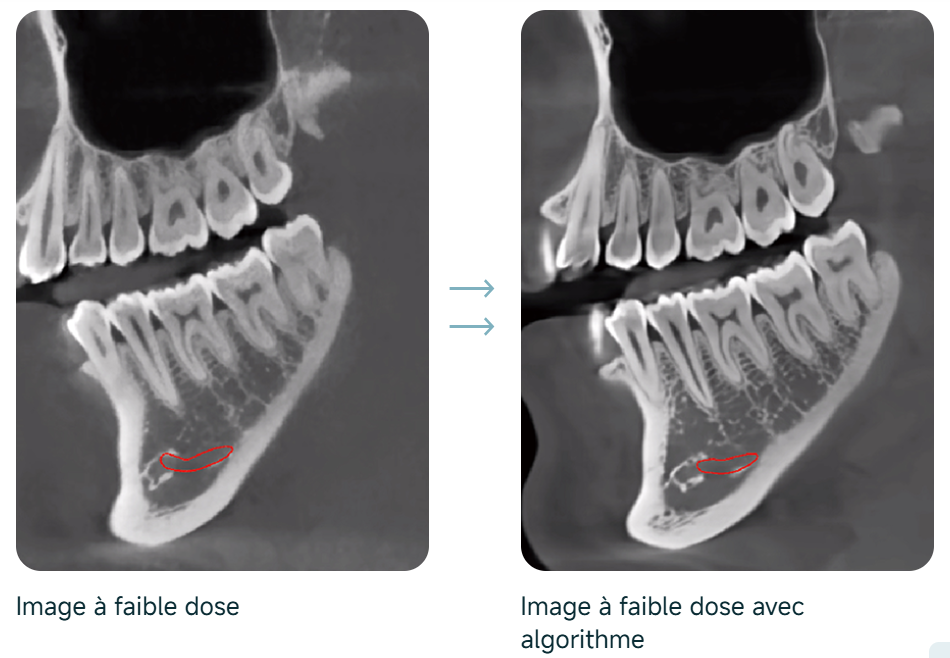

Suppression dynamique du bruit

Dose de rayons X ultra-faible et haute qualité d’image